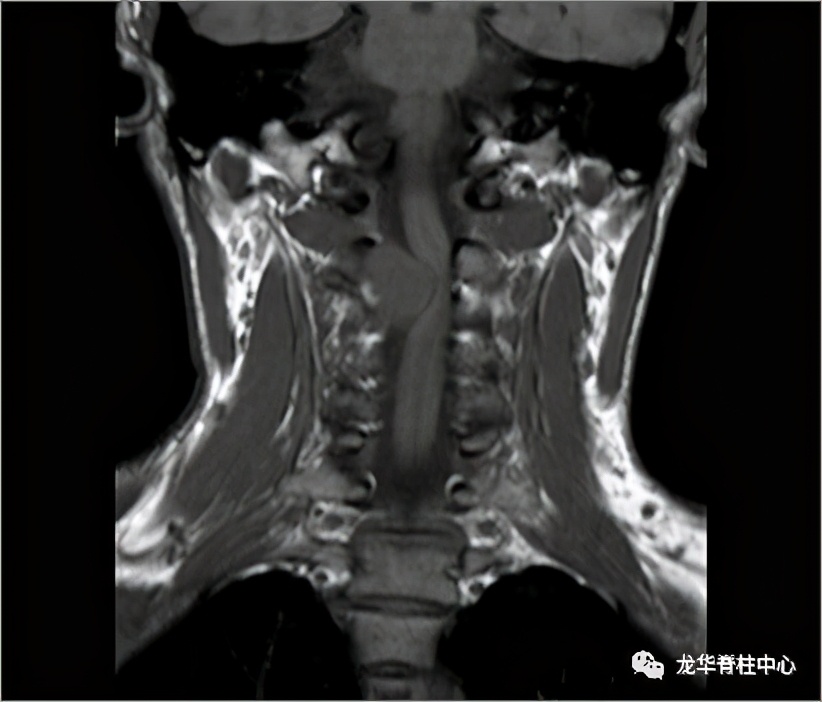

上颈椎椎管内外哑铃状肿瘤切除固定术